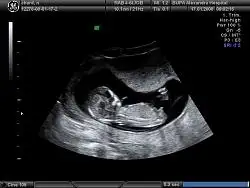

dr soylemeden siz gorun genital nub teorisi ( bebegin cinsiyeti)

Teyzeleri biziim içinde tahminde bulunur musunuzzzzz.......

Masallah cnm erkek bnce çikintı dik bide bas popo uzunluk oranı erkek fikrine kapılmma ndn oldu

evt bu resim icin erkek dedim cnm bnmm yukari bakio nub ucu